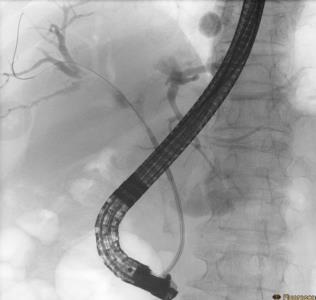

• 内镜射频消融术与光动力疗法治疗不可切除肝外胆管癌远期疗效的对比研究

2025, 31(7):11-18. DOI: 10.12235/E20240612

摘要 (180) HTML (124) PDF 946.36 K (300) 评论 (0) 收藏

摘要:目的 比较内镜射频消融术(RFA)与光动力疗法(PDT)联合胆道支架置入治疗不可切除肝外胆管癌的远期疗效。方法 回顾性分析2018年2月-2023年2月于该院接受内镜RFA或PDT治疗的胆管癌患者的临床资料,根据手术方法不同,将患者分为RFA组(n = 32,行内镜RFA联合胆道支架置入)和PDT组(n = 21,行内镜PDT联合胆道支架置入)。比较两组患者治疗次数、支架通畅期、总体生存期和并发症发生率,并分析影响患者生存期的危险因素。结果 RFA组与PDT组总体生存期分别为14.0(95%CI:11.8~16.2)和18.0(95%CI:15.4~20.6)个月,支架中位通畅期分别为4.0(95%CI:2.7~5.3)和3.5(95%CI:2.3~4.7)个月,差异均无统计学意义(P > 0.05);多因素Cox回归分析显示,内镜下RFA或PDT治疗次数的HR^ = 2.417,≥ 2次是影响总体生存期的保护性因素(P = 0.018),而TNM分期的HR^ = 0.300,Ⅲ期至Ⅳ期是影响总体生存期的危险性因素(P = 0.002);两组患者临床成功率均为100.00%;两组患者并发症总发生率[28.13%(9/32)和23.81%(5/21)]比较,差异无统计学意义(P > 0.05)。结论 内镜RFA与PDT联合胆道支架置入,治疗不可切除肝外胆管癌的远期疗效相似。内镜RFA或PDT序贯治疗 ≥ 2次,能够有效地延长患者的总体生存期。